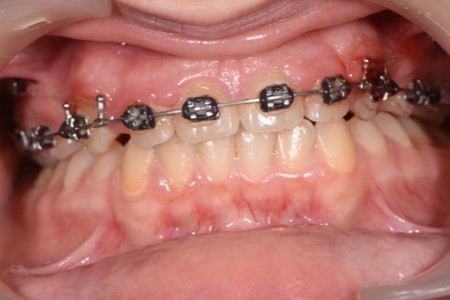

Figure 6.Significant overjet and overbite improvement after implant based orthodontic retraction.

The labial inclination of the incisors was corrected and better torque values were obtained. With the use of the temporary anchorage devices, a total of 7 mm of retraction was done in this case.

By moving the incisal edges backward, the upper lip position in regard to the upper frontal teeth was modified. The new position of upper teeth will play a major role in maintaining stability and preventing relapse. A more stable contact was obtained between the incisal edges of the lower anterior teeth and the palatal surface of the upper frontal teeth.